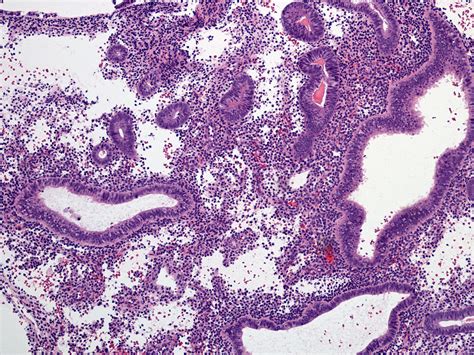

Weakly Proliferative Endometrium refers to a condition where the endometrium does not thicken adequately during the proliferative phase of the menstrual cycle. The proliferative phase is the first half of the menstrual cycle, during which the endometrium prepares for potential implantation of a fertilized egg. In a normal cycle, the endometrium thickens under the influence of estrogen. However, in cases of Weakly Proliferative Endometrium, this thickening is insufficient, which can impact fertility and overall reproductive health.

• Endometrial Biopsy: A small sample of the endometrium is taken for laboratory analysis to evaluate its structure and function.